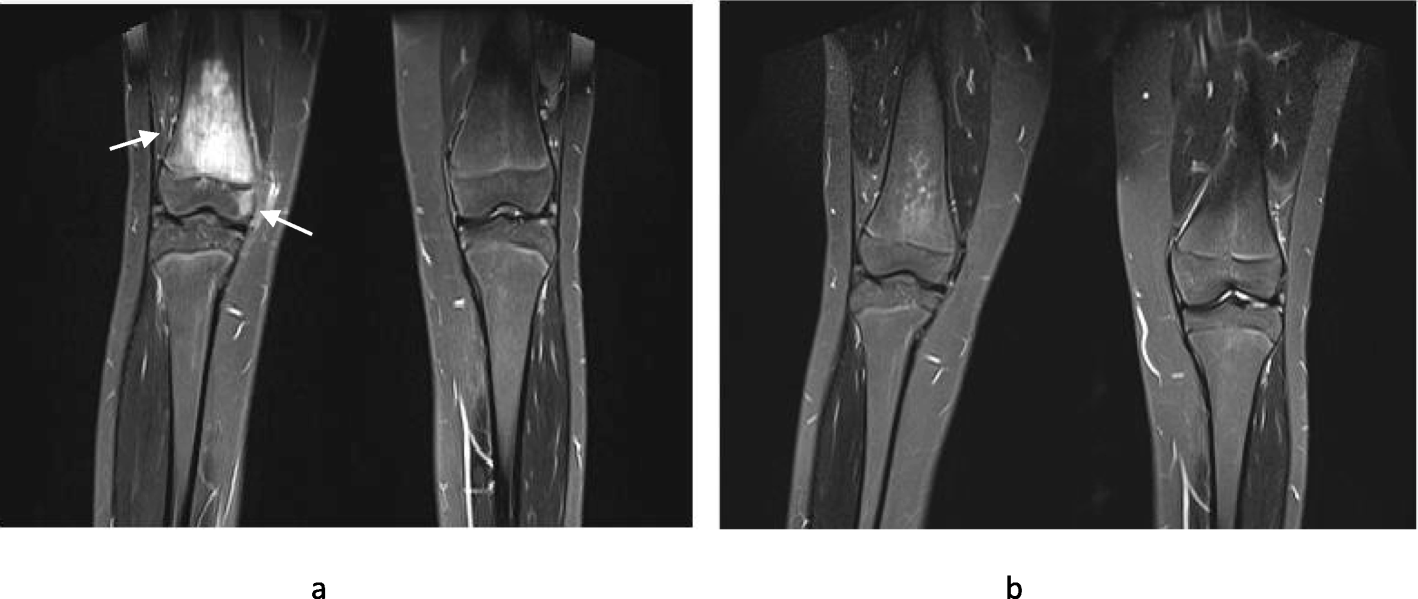

Fig. 2

Pre and post pamidronate treatment MR images. Pre and post- pamidronate WB-MRI images of a 15 year old girl who presented with significant right knee pain and was diagnosed with CNO following a bone biopsy. Her symptoms resolved completely following four cycles of pamidronate. 2a – The coronal STIR MR image shows extensive high signal predominantly of the distal right femoral metaphysis consistent with intra-osseus oedema. A smaller area of the medial epiphysis is affected without features of cortical destruction or significant soft tissue component. 2b – Almost complete resolution of the metaphyseal high signal is in keeping with treatment response. The epiphyseal component is also no longer visible. In our exercise, the machine algorithm and panel of radiologists concurred that lesions resolved post treatment